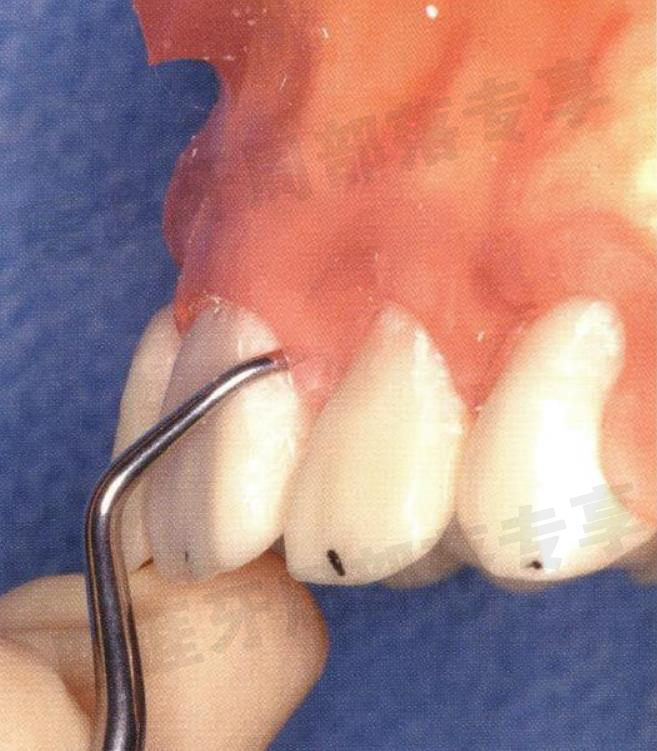

刃部放置于牙冠的接触点上,沿着接触点缓慢插入

怎么选洁牙器械5个要点带你学习器械洁牙_https://www.jmylbn.com_新闻资讯_第20张

怎么选洁牙器械5个要点带你学习器械洁牙_https://www.jmylbn.com_新闻资讯_第21张